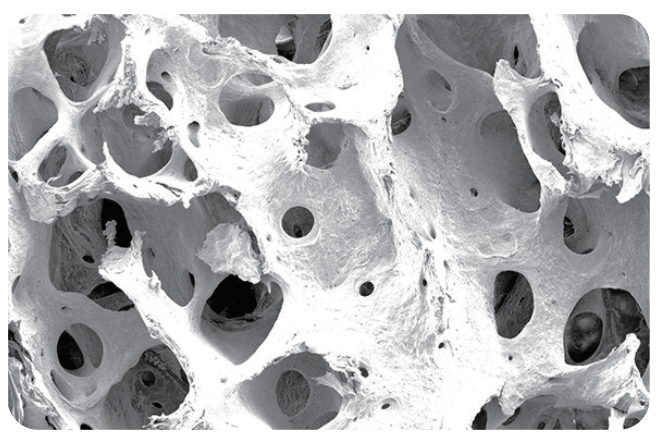

为牛松质骨经过脱细胞,脱脂等处理(易岭独特的专利技术[专利号:ZL202110089289.9])后形成的骨基质,属于脱细胞基质类再生材料,呈白色略带黄色块状或颗粒状,保留了天然的三维多孔结构,主要成分是I型胶原蛋白。

诚谷快口腔用骨填充材料采用前沿的创新工艺,精细地保留了动物组织的原生三维微观结构,因此具有出色的抗压性能,具有足够支撑力对抗粘膜压力,为骨组织重建提供稳定支撑和足够空间,促进骨组织重建。

双峰多孔结构,孔隙率高达80%,优化了材料的毛细作用,同时保障了血液中成骨细胞和生长因子的募集,确保有效骨融合。

诚谷快@口腔用骨填充材料和人体骨组织结构高度相似,为血管再生和新骨沉积(成骨)提供充足空间。多种直径微孔隧道结构技术保证了诚谷快口腔用骨填充材料良好的毛细作用,从而能迅速摄取液体(血液);相互连通大孔允许各种细胞和生长因子进入,结合并储存蛋白质和生长因子,为骨融合提供了必要的生物环境和生长因子支持引导自体骨的自然改建。